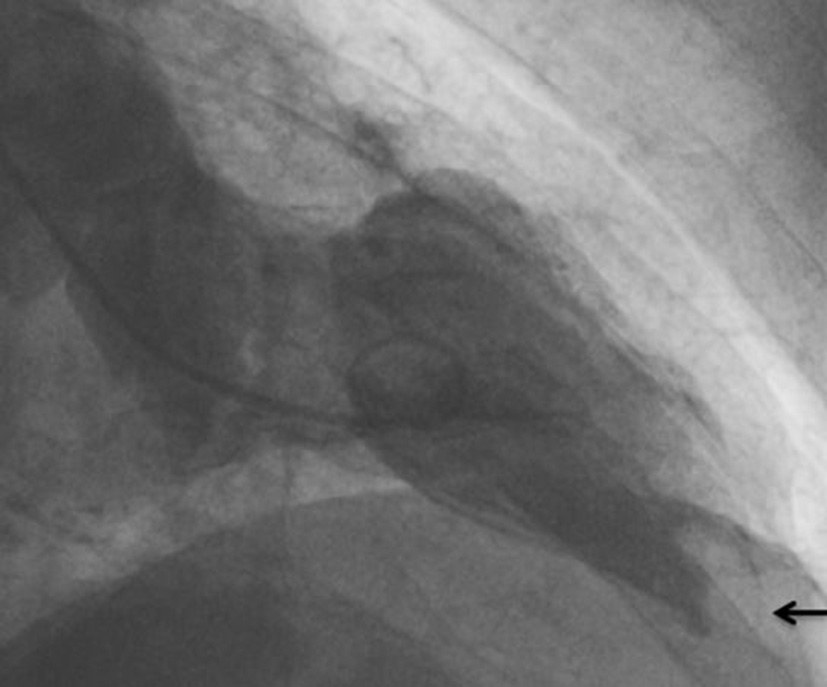

Ventriculography showed a moderately reduced global LV function (ejection fraction of 40%) with apical and septal akinesia. In addition, a thrombus (16 mm diameter) was clearly visualized in the apical part of the left ventricle (Figure 2).

Figure 2

Thrombus (arrow) in the apical part of the left ventricle as demonstrated by ventriculography.